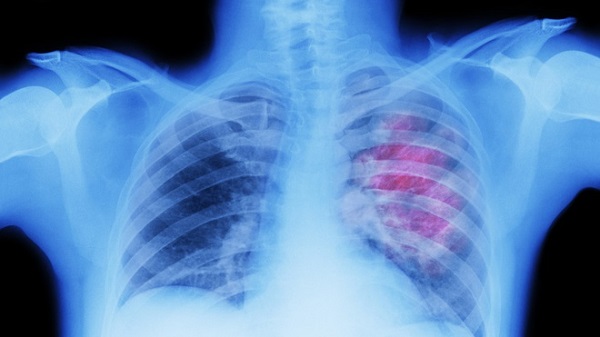

14 bệnh nhân Covid-19 trở về từ Bangladesh, có 7 bệnh nhân có biểu hiện viêm phổi, được thể hiện qua các biểu hiện lâm sàng và dấu hiệu tổn thương trên phim chụp.

Nghiên cứu về tình trạng thủng phổi ở bệnh nhân mắc Covid-19

Các nhà khoa học của Đại học Cambridge (Anh) vừa công bố kết quả nghiên cứu về tình trạng thủng phổi ở bệnh nhân mắc Covid-19. Theo RT, nhóm đánh giá biến chứng này gây phức tạp cho quá trình điều trị và ảnh hưởng lâu dài tới sức khỏe của người mắc Covid-19.